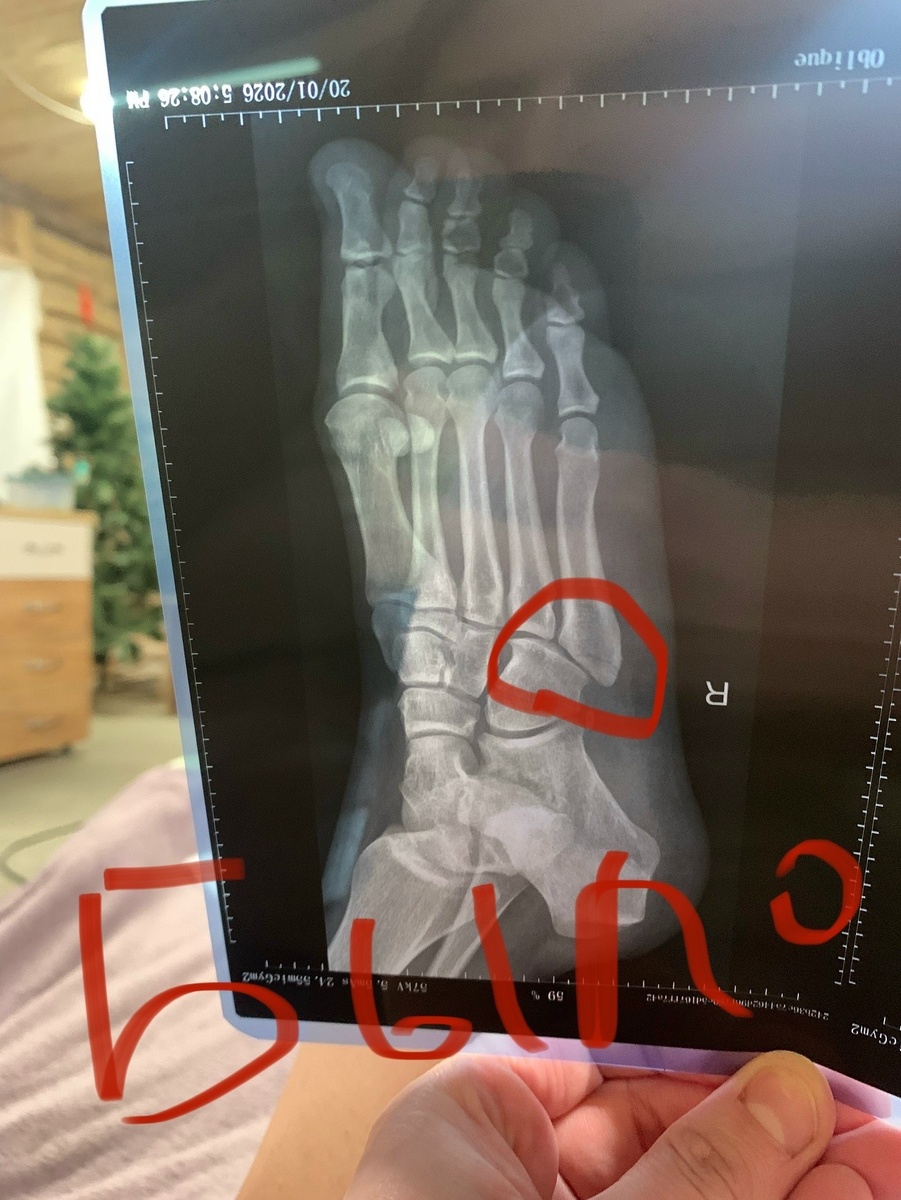

ЖИЗНЬ НАЛАЖИВАЕТСЯ!!! Скоро бегать буду, за собаками да кошками)))

И самое главное! ВОЗМОЖНО, если я буду аккуратна и всё пойдет как сейчас хорошо, то через 1.5 месяца я смогу бегать, прыгать что зайчонка, КОПАТЬ. Копать для меня самый главный пунктик - забор для собачек делать душа

И самое главное! ВОЗМОЖНО, если я буду аккуратна и всё пойдет как сейчас хорошо, то через 1.5 месяца я смогу бегать, прыгать что зайчонка, КОПАТЬ. Копать для меня самый главный пунктик - забор для собачек делать душа желает!!!